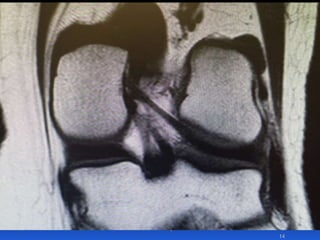

Diagnosis 1

MRI & PCL

Clinical examination is more reliable than MRI

scan

The PCL may be dysfunctional despite normal MRI

Kneeling stress x-ray shows the degree of posterior

translation